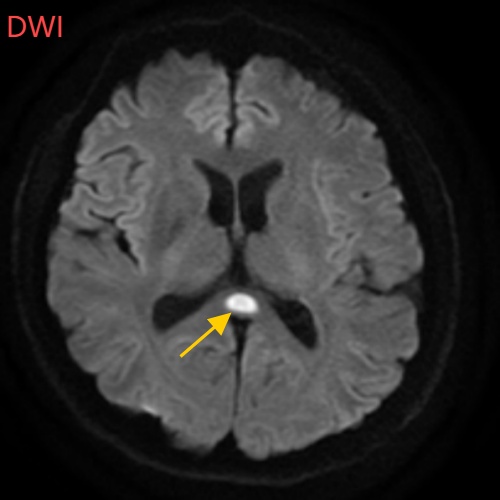

董先生再次来到南科大医院,入神经内科住院治疗。经过头部磁共振平扫、弥散、增强影像等检查,医生诊断,董先生得了比较少见的病症:可逆性胼胝体压部综合征。

董先生的5月2日影像结果显示,胼胝体压部发生病变

据神经内科白春艳主任医师介绍,可逆性胼胝体压部综合征以胼胝体压部短暂性病变为特征,患者可能表现为头痛、意识障碍、精神行为异常、癫痫发作等相关症状。